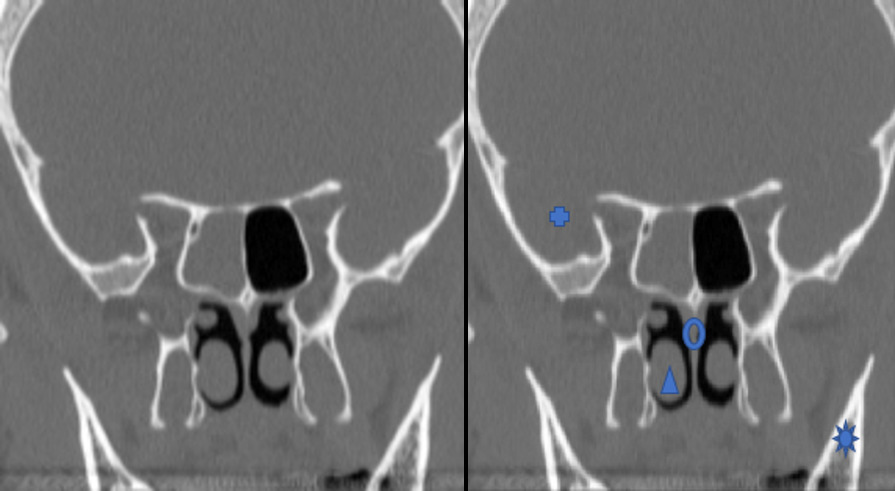

Le scanner en coupe frontale osseuse montre un comblement complet du sinus sphénoïdal droit, témoignant d’une sphénoïdite aigue ou chronique. Un élément scanographique qui pourrait orienter vers l’étiologie chronique est l’épaississement des parois sinusiennes. Le bilan biologique témoigne d’un syndrome inflammatoire aigu avec hyperleucocytose et augmentation de la PCT et de la CRP.